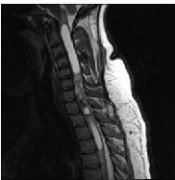

頸椎椎管內(nèi)腫瘤有什么癥狀?出國(guó)看病怎么治?

頸椎椎管內(nèi)腫瘤有什么癥狀?出國(guó)看病怎么治? 頸椎椎管內(nèi)腫瘤有什么癥狀?根據(jù)在椎管內(nèi)的位置不同,分為三大類: 脊髓髓外硬膜內(nèi)腫瘤 、脊髓內(nèi)腫瘤和椎管內(nèi)硬膜外腫瘤。 長(zhǎng)在不...